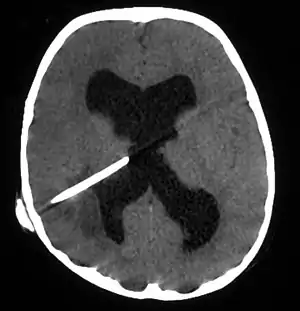

Brain abscess in a person with a CSF shunt.[1]

The diagnosis is established by a computed tomography (CT) (with contrast) examination. At the initial phase of the inflammation (which is referred to as cerebritis), the immature lesion does not have a capsule and it may be difficult to distinguish it from other space-occupying lesions or infarcts of the brain. Within 4–5 days the inflammation and the concomitant dead brain tissue are surrounded with a capsule, which gives the lesion the famous ring-enhancing lesion appearance on CT examination with contrast (since intravenously applied contrast material can not pass through the capsule, it is collected around the lesion and looks as a ring surrounding the relatively dark lesion). Lumbar puncture procedure, which is performed in many infectious disorders of the central nervous system is contraindicated in this condition (as it is in all space-occupying lesions of the brain) because removing a certain portion of the cerebrospinal fluid may alter the concrete intracranial pressure balances and causes the brain tissue to move across structures within the skull (brain herniation).

Ring enhancement may also be observed in cerebral hemorrhages (bleeding) and some brain tumors. However, in the presence of the rapidly progressive course with fever, focal neurologic findings (hemiparesis, aphasia etc.) and signs of increased intracranial pressure, the most likely diagnosis should be the brain abscess.